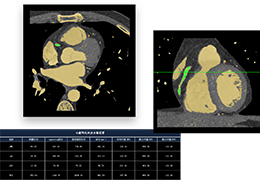

ART-Plan™ Artificial Intelligence Contouring